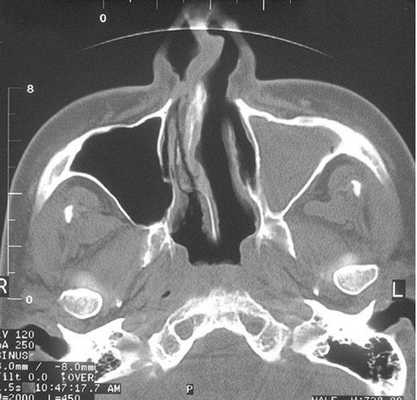

При наличии у пациента симптомов острого синусита КТ верхней челюсти и гайморовых пазух, в основном, проводят без контраста. На нативных изображениях отчетливо видны:

краевое пристеночное утолщение слизистой (за счет отека и инфильтрации);

утолщение внутренних структур носа;

наличие и уровень экссудата в полости каверны;

сужение выводных протоков.

При прогрессировании воспалительного процесса отечная слизистая оболочка или воспалительный секрет могут целиком закрыть просвет пазухи, что также покажут снимки.

КТ верхней челюсти отображает наличие жидкости в полости и позволяет оценить ее плотность. Повышенная плотность содержимого пазухи указывает на гнойные формы острого синусита.